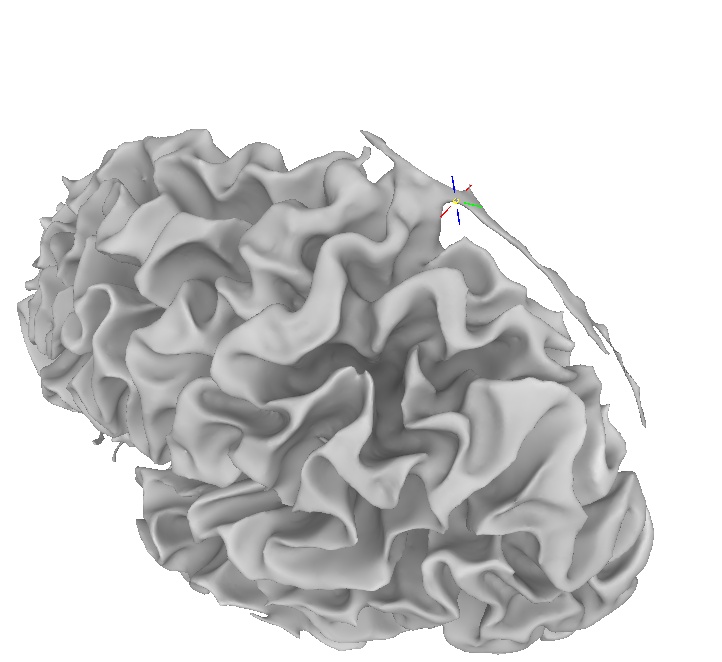

What if I have created a surface model and it looks bad?

Sometimes the cortical surface model created by FreeSurfer contains large errors.

For instance, in this picture, part of the pia-arachnoid-dura has been classified as part of the cortex.

Then, rerun the surface creation routine.